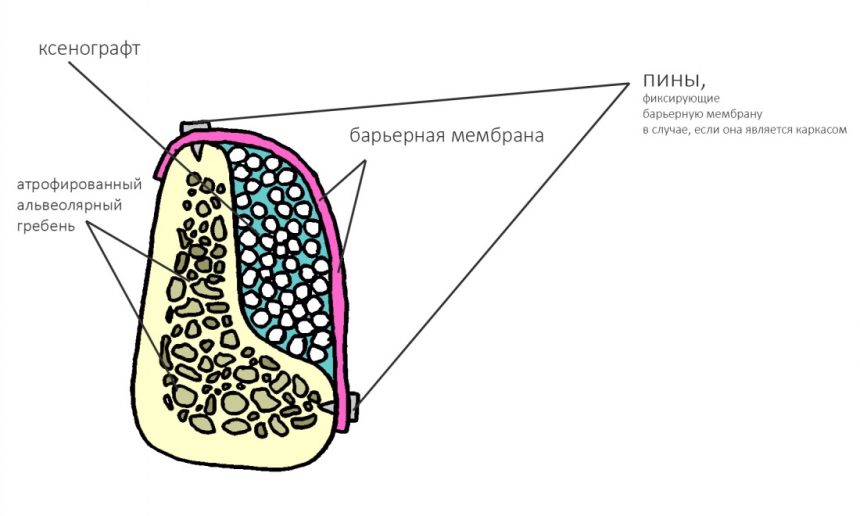

мембранная аугментация — один из вариантов каркасной методики НКР с резорбируемым каркасом:

а использование титановой сетки — та же НКР, но уже каркасная нерезорбируемая:

Барьерные мембраны

Не акцентируя внимания на производителях и материалах, все существующие барьерные мембраны можно разделить на две большие группы: резорбируемые и не резорбируемые. В последнее время появились еще т. н. «полурезорбируемые» мембраны, т. е. с длинным сроком резорбции, но один фиг — они всё равно рано или поздно резорбируются так, что являются резорбируемыми.

Вопреки распространенному мнению, именно барьерные мембраны являются самым главным расходником при остеопластике. Потому, что используются не только при НКР:

но и, в некоторых случаях, при аутотрансплантации крупных костных фрагментов:

Чтобы понять, как работает барьерная мембрана, нужно вспомнить, что все ткани регенерируют с разной скоростью. В частности, миграция остеобластов, их дифференцировка, формирование костной мозоли, минерализация и окончательная перестройка кости происходит крайне медленно, в отличие от слизистой оболочки и других тканей (за исключением разве, что нервной). И, если мы хотим образования кости в обозначенном пространстве, нам необходимо чем-то отделить его от быстрорастущих мягких тканей. Причём, сделать это можно, буквально, всем, чем угодно: от специальной фольги до свободного соединительнотканного трасплантата. Правда, последним очень сложно работать.

Итак, первая функция барьерной мембраны — это изоляция:

Кроме того, современные барьерные мембраны обладают такой прочностью, что могут сами по себе играть роль каркаса:

Это активно используется в различных методиках направленной костной регенерации:

Однако, под действием развивающегося отека, под действием мышц или внешнего давления, барьерная мембрана может сместиться, а форма графта под ней — деформироваться. Поэтому, если барьерная мембрана является контурирующим элементом, её необходимо фиксировать пинами или винтами:

Это не всегда легко сделать, особенно с язычной или небной стороны, поэтому в последнее время мы вместо пинов используем швы. Сути дела это не меняет:

Барьерная мембрана может играть две роли, изолирующую и контурирующую.

В случае, если контур будущего альвеолярного отростка задается какими-то другими элементами (блоком, пластиной, сеткой и т. д.), в фиксации большинства мембран нет необходимости

Если же барьерная мембрана сама по себе является каркасом (например, при НКР), то ее обязательно нужно фиксировать любым доступным способом.